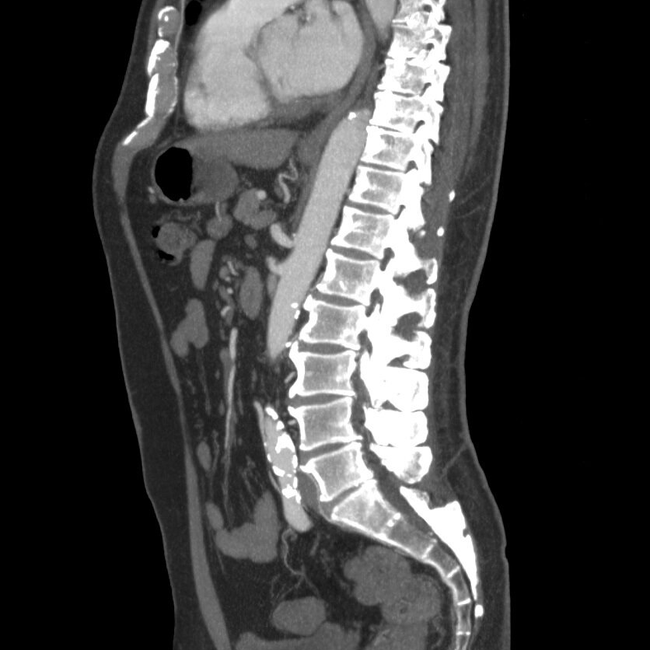

МРТ шейного отдела позвоночника: ключевые моменты и что ожидать